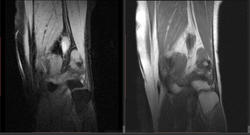

Мужчина 1963 г.р. Жалуется на боль в левом коленном суставе около 6 мес, в последний месяц стало совсем тяжко. Со слов заболел зимой, когда во время прогулки коленки сильно замерзли. Сам думаю на асептический некроз, но смущает множественность поражения.

Дмитрий, я в заболеваниях суставов не дока, но трабекулярный отек вкупе с выпотом может быть обусловлен воспалительными изменениями , но полностью начальные проявления аваскулярного некроза не могу отрицать.

я бы не поставил аваскулярный некроз. если исключена травма, дифференцировать с артритом.

Хрящ не поврежден, для артрита...